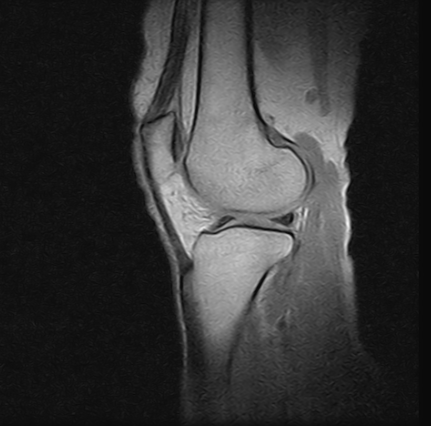

Ressonâncias Magnéticas Joelho

Se você pesquisa ressonâncias magnéticas joelho com eficiência e profissionalismo, não deixe de vir conhecer os serviços oferecidos pela RM Brasil.